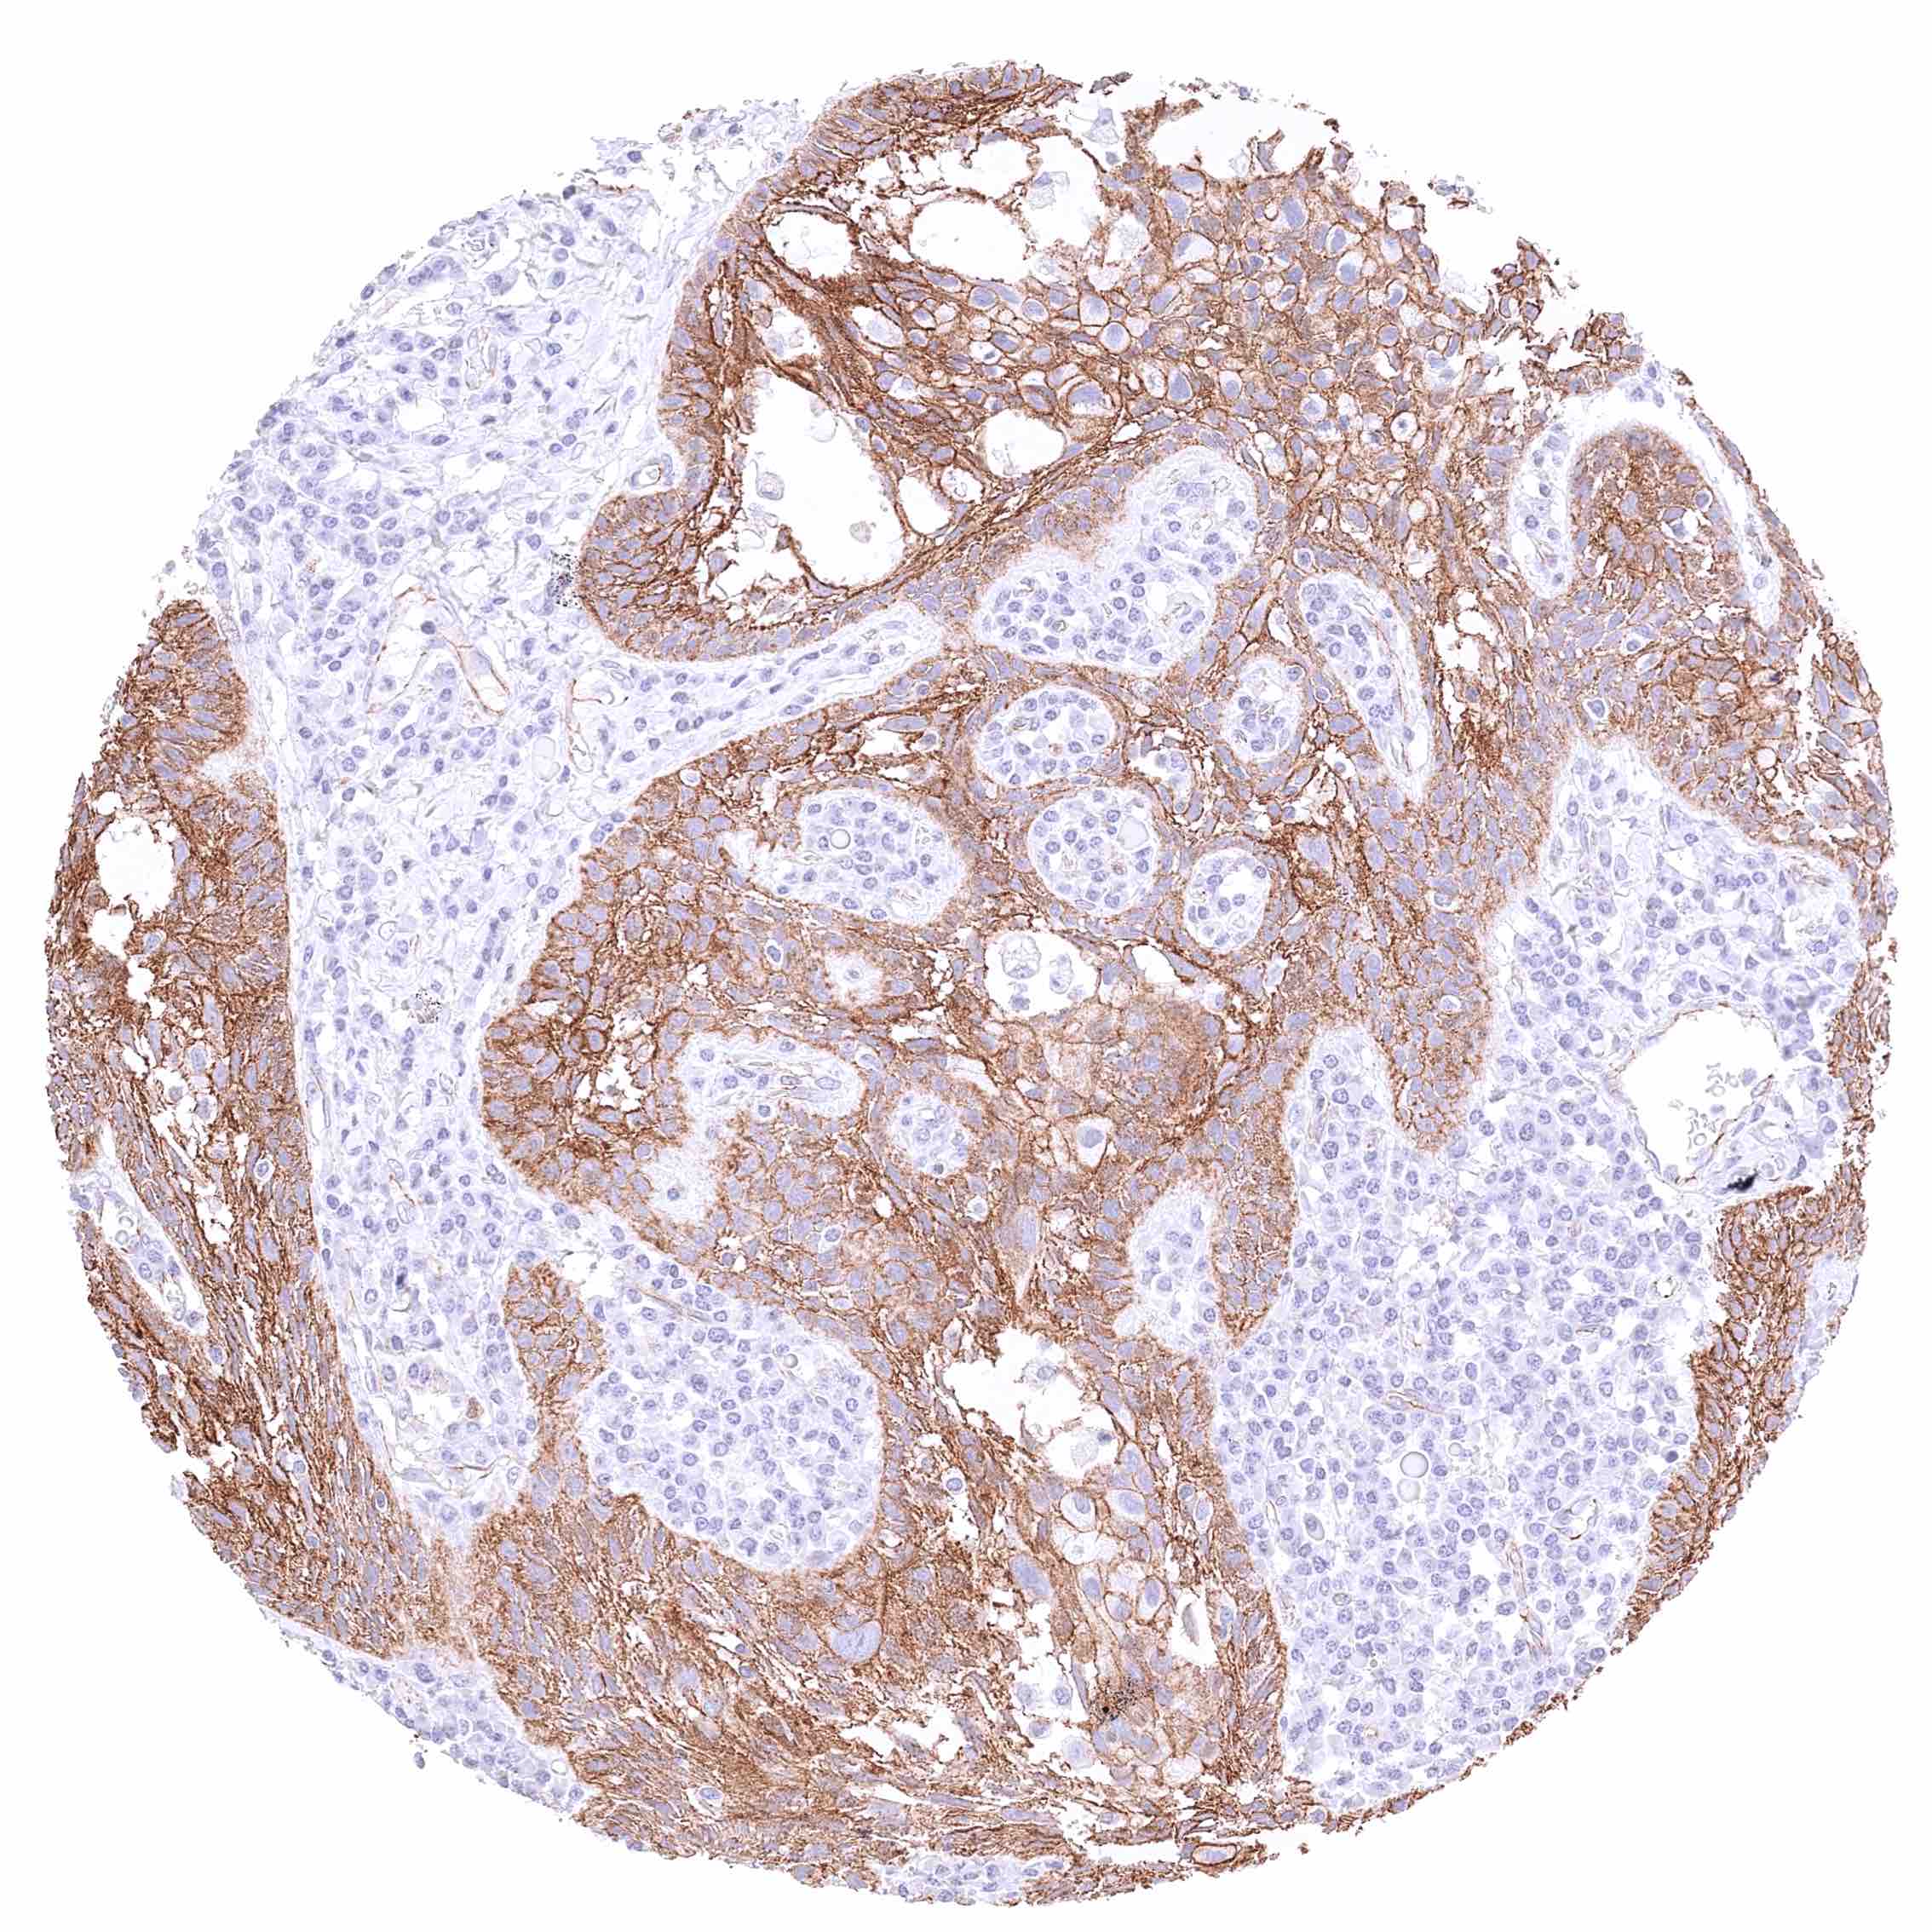

Prostate – Adenocarcinoma (Gleason 4+4=8) with strong membranous, moderate cytoplasmic, and strong nuclear β-Catenin staining of tumor cells.